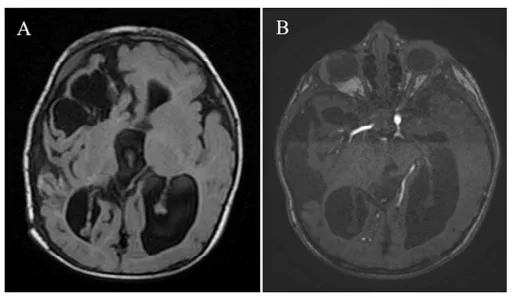

胎儿MRI发现右侧大脑半球巨大血管病变,压迫邻近脑实质,致中线结构向对侧移位,还出现早期梗阻性脑积水(图1A-B)。还好的是,胎儿生命体征稳定,因此医生决定等待胎儿出生后再进行治疗。

图1A-B